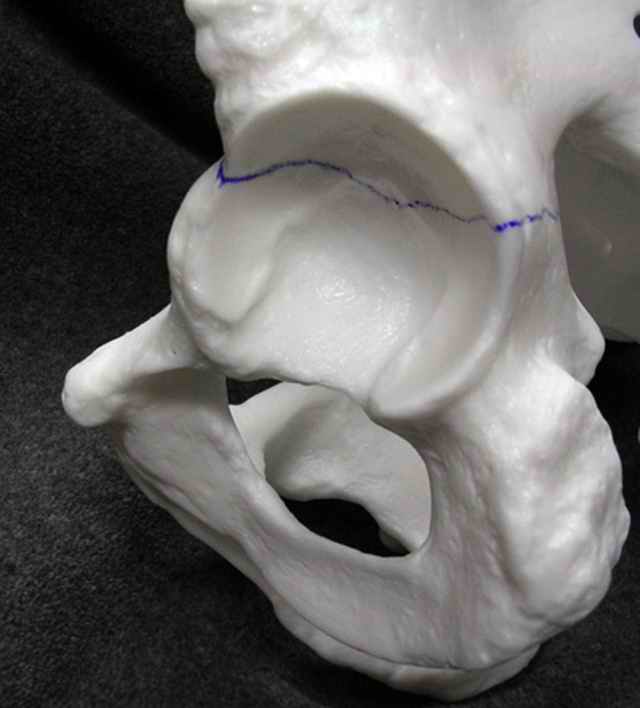

If you¹d examine any routine CT scan of a normal non-variant pattern transverse fracture, and imagine where you¹d place your ideal clamp for compression of the fracture line, then it¹s typically with one tine applied to the quadrilateral surface and the other tine applied in the area between the AIIS and the posterior wall (or the wall itself in some instances)... the

pictures will ³make more sense².

If you¹d simply elevate the periosteum of the greater notch, then work thru the notch to elevate the obturator internus from the quadrilateral surface, then you can palpate thru the notch the transverse fracture offset/displacement at the quadrilateral surface and often all the way to

the anterior column. You can then lateralize/lengthen the caudal transverse segment uniformly however you¹d choose and clamp it thru the notch... then palpate thru the notch to better assess the near entirety of the transverse fracture... the C-arm images confirm the restoration of the 3 line landmarks and you can adjust the C-arm beam to be tangential to the true fracture line if you¹re still in disbelief that you¹ve finally gotten a transverse reduction!! The transverse¹s anterior column component can next be